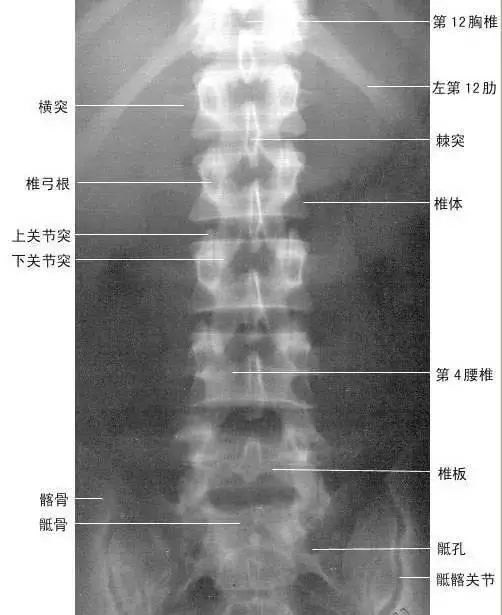

【实用干货】人体体表标志定位与解剖(含人体解剖图)